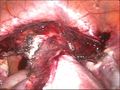

uterus before hysterectomy

-